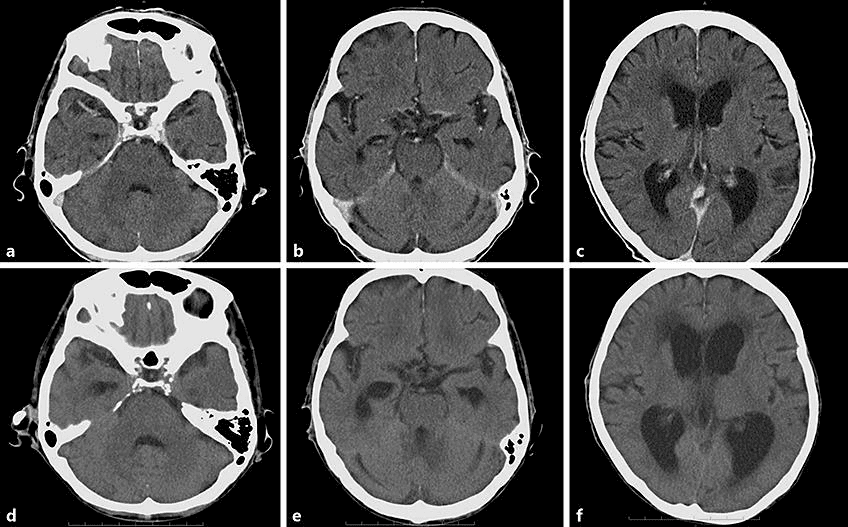

Fast and detailed diagnosis with Brain CT! MR imaging and CT scanning services with expert radiologists and advanced technology. Check-up packages with the medical imaging center difference!